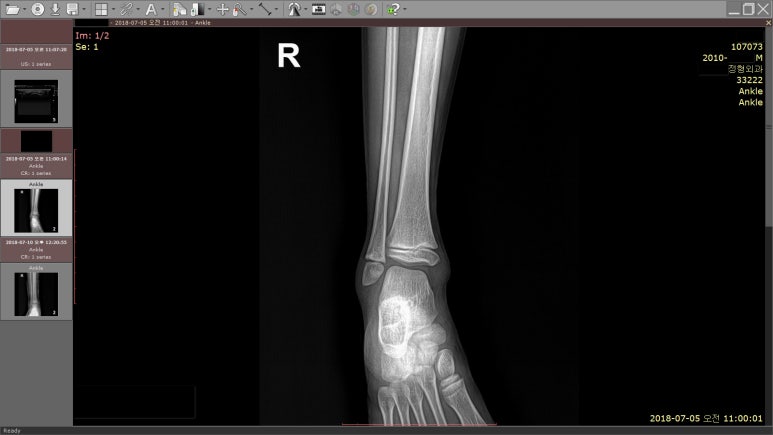

해당 환자의 X-RAY / MSK USG 영상

결과는?

초음파 검사상

견열골절로 진단받고,

통깁스도 하였습니다.